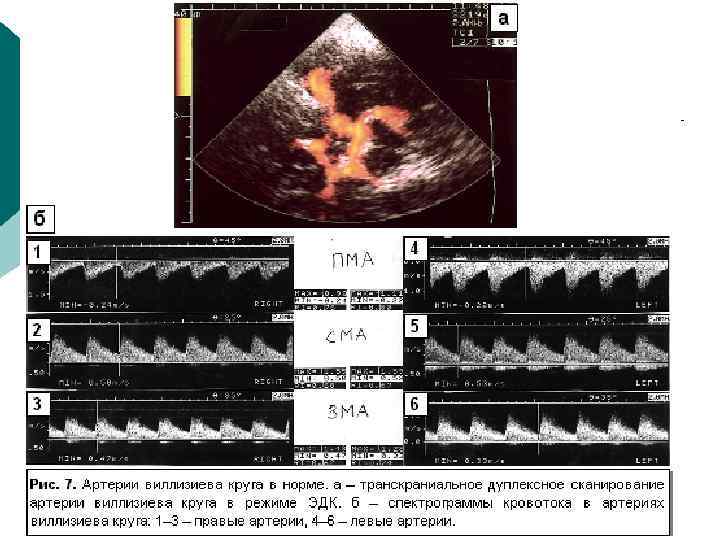

Апикальная позиция Апикальное четырехкамерпое сечение: а — эхокардиограмма; б-схема (ПЖ — правый желудочек, ЛЖ — левый желудочек, ТК-трехстворчатый кланам, МК — митральный клапан, ПП — правое предсердие, ЛП-левое предсердие